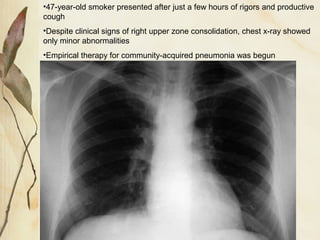

•47-year-old smoker presented after just a few hours of rigors and productive

cough

•Despite clinical signs of right upper zone consolidation, chest x-ray showed

only minor abnormalities

•Empirical therapy for community-acquired pneumonia was begun